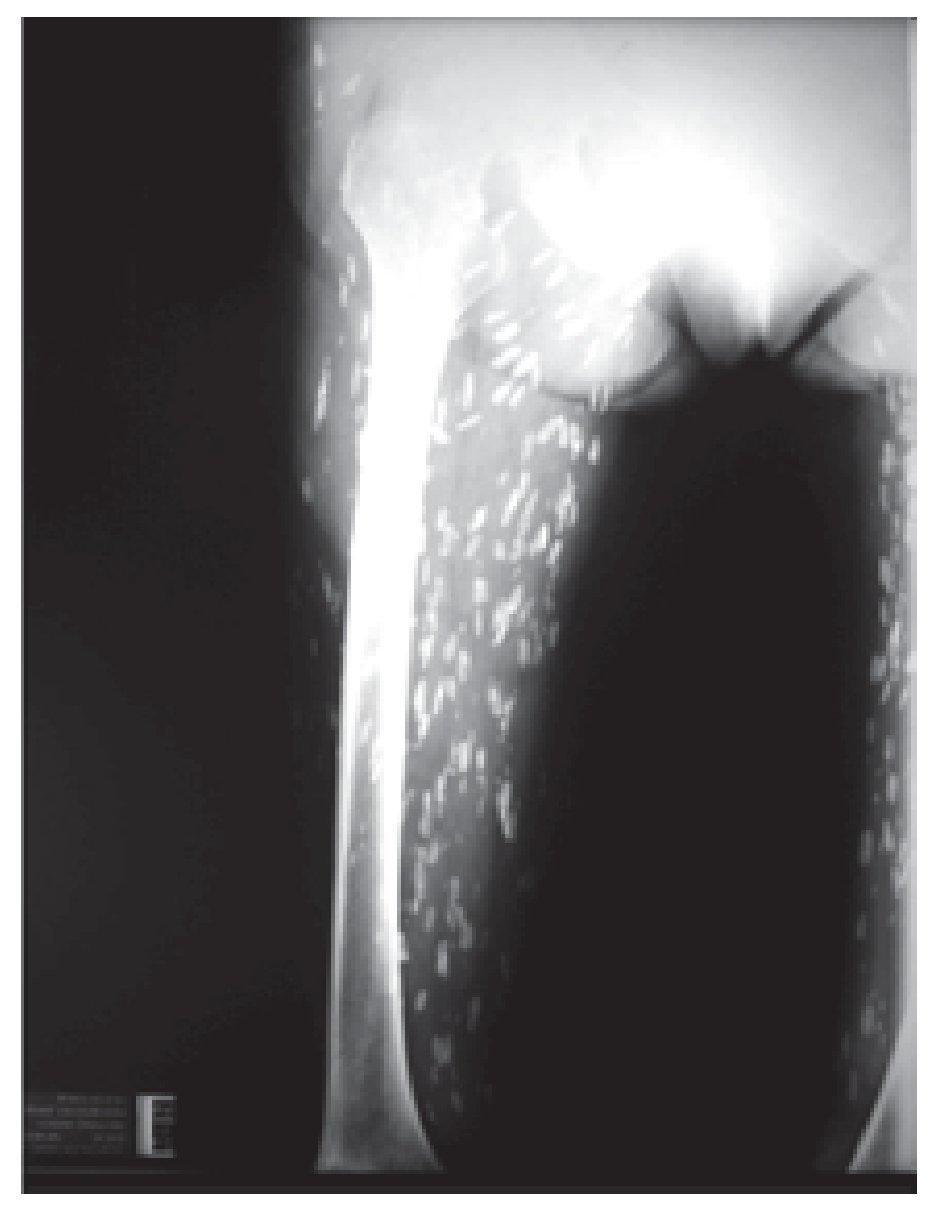

Mujer de 88 años, procedente de Zacatecas, enviada por diarrea, flatulencia y dolor cólico abdominal intermitentes, con duración de uno a dos días por semana, asociados claramente con la ingesta de productos lácteos. Refirió también polimialgia difusa y continua, todo con más de 10 años de evolución. Nunca antes había acudido con un médico por esta sintomatología. La paciente solía elaborar productos cárnicos que consumían en casa y uno de sus hijos fue operado de cisticercosis cerebral. Contaba con una radiografía simple de abdomen (Figura 1). Al ver la imagen radiográfica y correlacionarla con las polimialgias, se solicitaron radiografías de tórax y miembro pélvico (Figuras 2-4), reacción a la cisticercosis (ELISA) con resultado negativo, y dos biopsias del músculo donde habían calcificaciones. El informe de patología señaló nódulo encapsulado con calcificación difusa, compatible con parasitosis, cuya calcificación del contenido dificulta determinar el tipo de parásito; músculo esquelético con cambios reactivos y tejido fibro-conectivo y adiposo con arterioesclerosis de Möckenberg.

¿ Figura 4. Evidencia radiográfica de múltiples calcificaciones.

Existe poca información sobre la cisticercosis diseminada, pero se considera una entidad rara. La reacción a la cisticercosis resulta negativa en estos casos, debido a que no hay parásitos vivos y las polimialgias se deben a reacción inflamatoria en respuesta a las calcificaciones. La información sobre miopatía o miositis por cisticercosis muscular diseminada es muy escasa, pero al tratarse de una infección inactiva, el tratamiento es sólo sintomático con base en antiinflamatorios no esteroideos o analgésicos de acuerdo a los requerimientos del enfermo.